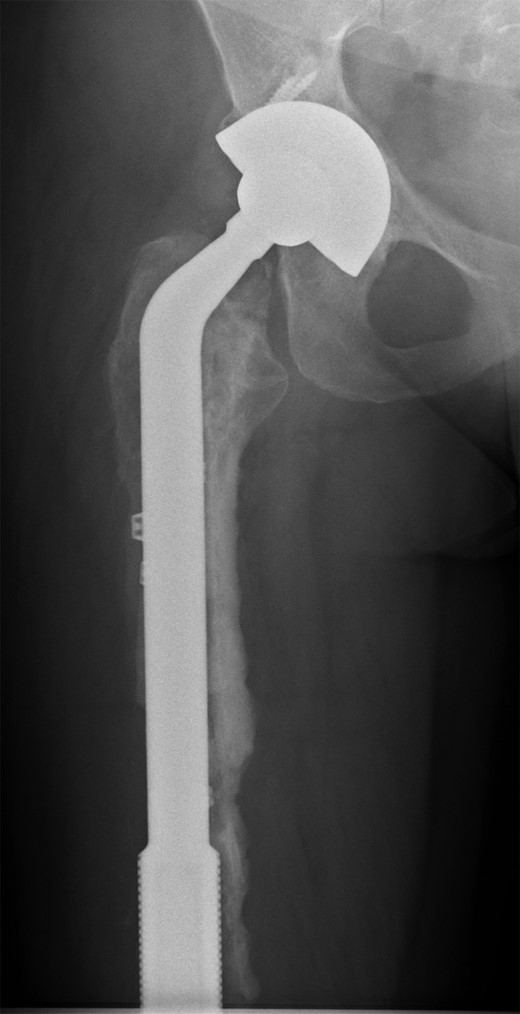

She subsequently sustained a periprosthetic fracture at the distal tip of her right total hip replacement (Fig. 1). An initial attempt was made to manage this fracture with a plate and Dall-Miles cables (Fig. 2); however, the fracture did not unite. The patient went on to have a custom-made cement-linked internal proximal femoral replacement, which had a hollow cylindrical design to accept the stem of the existing well-fixed distal femoral component (Figs 3 and 4). This linked prosthesis effectively converted her separate prostheses to a total femoral replacement, sparing her distal femoral replacement from revision. She had no problems postoperatively and recovered well from her surgery.

Plate and Dall-Miles cable fixation of periprosthetic fracture.